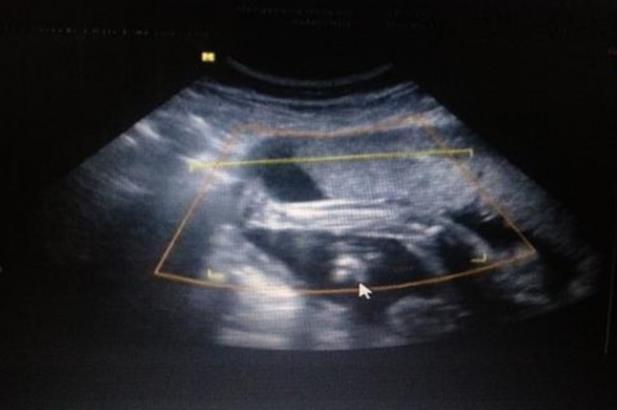

二胎寶寶,第一胎在六年前到時真的是糊里糊涂的,出血以為是來例假了,后面才發(fā)現(xiàn)是懷孕,沒有驗過孕酮,只照了兩次B超,還有一次還是因為被同事說了前三個月要多注意又去照的,大寶就這么順順利利剖腹出來了,女寶。現(xiàn)在二胎多了好多流程,有可能是年齡的原因,孕酮偏低,但是雌二醇和HCG正常增長,每次驗都下降,第一次75,第二次59,第三次57,第四次49.6,第五次49.8,20天內(nèi)驗了5次血,打針吃藥不停,昨天B超有胎心胎芽的,終于放心多了,現(xiàn)在是用中西醫(yī)結合的方法保胎。